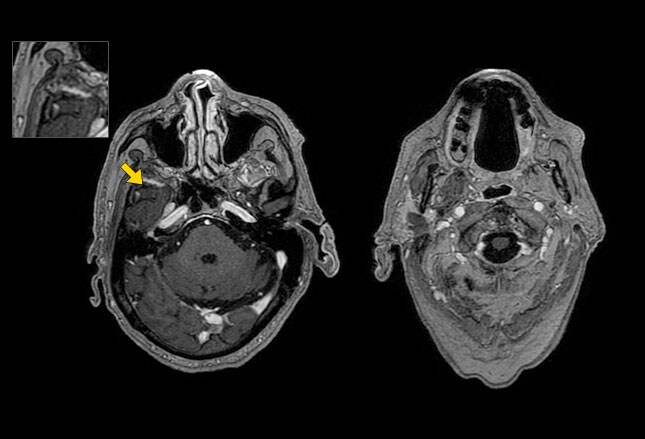

Facial nerve tumor

Facial nerve tumor 114 photos